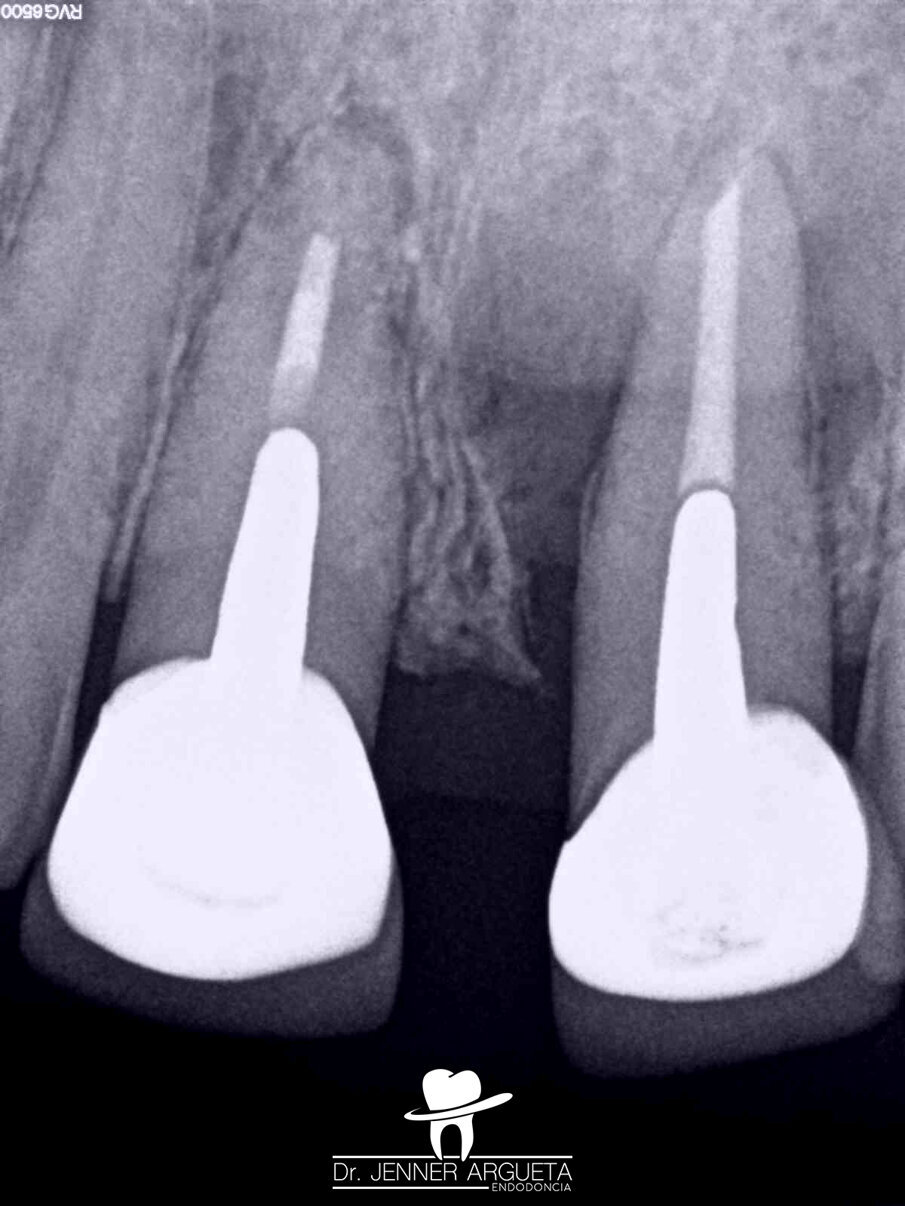

A 50-year-old male patient presented to the dental office with Grade III mobility and intra-oral swelling affecting tooth #21. The patient also reported pain when biting on tooth #11 (Fig. 9). The established diagnosis for tooth #21 was previously treated and acute periapical abscess; cemental tears at mesial and distal root surfaces were detected, as well as a root fracture. The established diagnosis for tooth #11 was previously treated and symptomatic periapical periodontitis.

Tooth #21 was extracted, and a bone grafting material (DM Bone, Meta Biomed) was placed in the area to prepare the site for receiving an implant in the future (Fig. 10). Four weeks after the extraction, periapical surgery was performed on tooth #11, and the minimum amount of root was resected in order to avoid compromising the crown–root ratio. The retro-cavity was prepared using ultrasonic tips (Fig. 11), and CeraPutty was used to retro-obturate the root (Figs. 12 & 13). The sutures were removed five days after surgery (Fig. 14a–c). The four-month follow-up radiograph showed the process of healing in both treated areas (Fig. 15).

Fig. 12: Retro-obturation of tooth #11 during periapical surgery using CeraPutty.

Fig. 13: Radiograph after periapical surgery showing the well-adapted and dense retro-obturation.